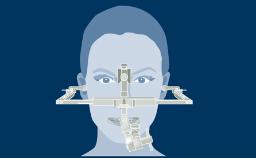

The use of dental implants has become a standard treatment in many clinical situations. However, in order to achieve optimal functional and esthetic results, the clinician has to assess the complexity and risks associated with an implant therapy before starting the treatment.

The SAC classification system differentiates between Straightforward, Advanced and Complex treatments. It was first proposed in a textbook on minor oral surgery for general dentists. In a Consensus Conference in 2007, the ITI reviewed and refined the SAC Classification for use in implant dentistry. The proceedings were published in a text book in 2009 and since then serve as an important tool in implant dentistry.